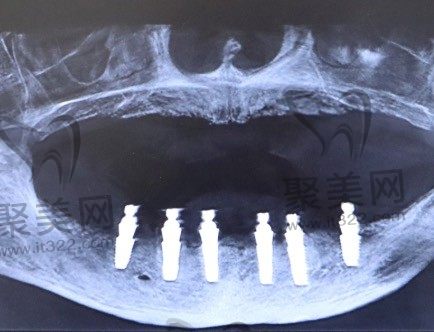

半口牙种植指的是一种以植入骨组织内的下部结构为基础来支持、固位上部牙修复体的缺牙修复方式。它包括下部的支持种植体和上部的牙修复体两部分。它采用人工材料(如金属、陶瓷等)制成种植体(一般类似牙根形态),经手术方法植入组织内(通常是上下颌)并获得骨组织牢固的固位支持,通过特殊的装置和方式连接支持上部的牙修复体。

半口种植牙的全过程,包括位置的选定,粘膜切开,备洞钻孔,种植体植入,最后的粘膜缝合的过程。在进行种植牙治疗时,位置的选择非常关键,需要选择在骨质较好的位置,进行粘膜切开后选择骨质条件好的位置进行种植窝洞的制备,按照骨头的宽度,高度及长度选择合适直径的种植体进行植入,最后进行粘膜的缝合。全口或半口种植牙后,在保证一定的骨结合和初期稳定性后,可以选择即可修复来恢复牙齿的咀嚼。